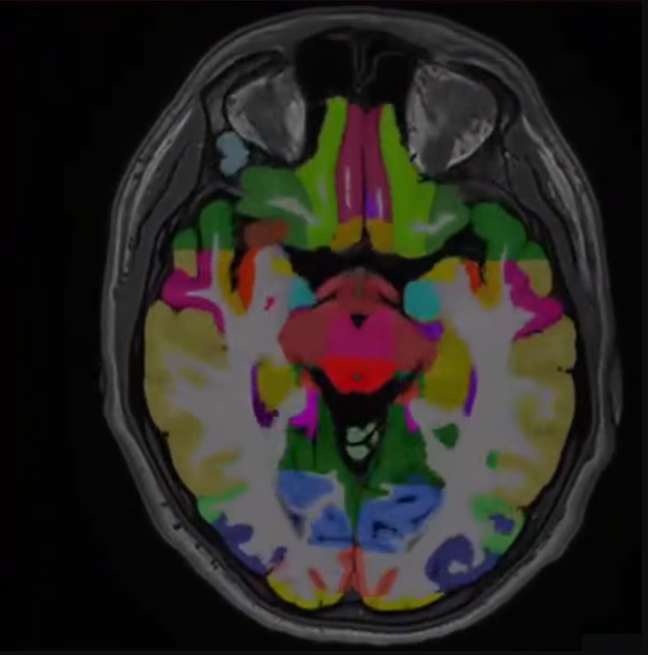

Volumetric Quantification

An advanced diagnostic tool that aids in the diagnosis of TBIs by combining MRI data with clinical and cognitive test results. It detects subtle brain abnormalities, differentiates injury severities, and tracks disease progression using AI-driven pattern recognition and reference population comparisons.

The prevalence of Alzheimer’s is increasing; 5.8 million people were estimated to have the condition in 2020, and it is projected to impact 14 million by 2060. Using volumetric quantification of 133 brain areas, Advanced Imaging Reno provides deeper insight into your brain. The density of different regions and patterns of density loss are compared.